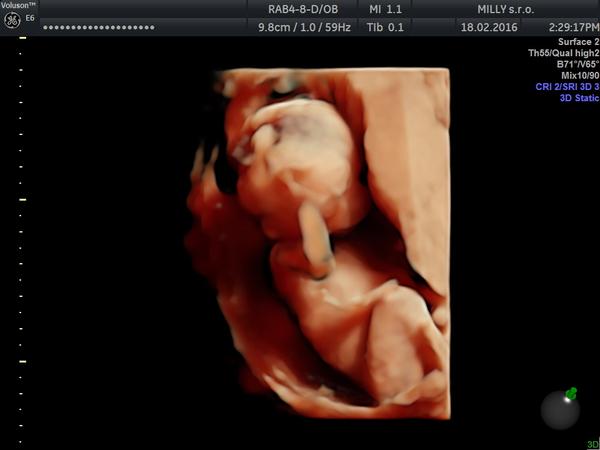

@nikus47 tak takéto foto som ešte nevidela...... krásne... veľa zdravíčka a potešenia!

@nikus47 jeeeeeej prenadherny obrazok 🙂 Nech ja zdravucky 🙂